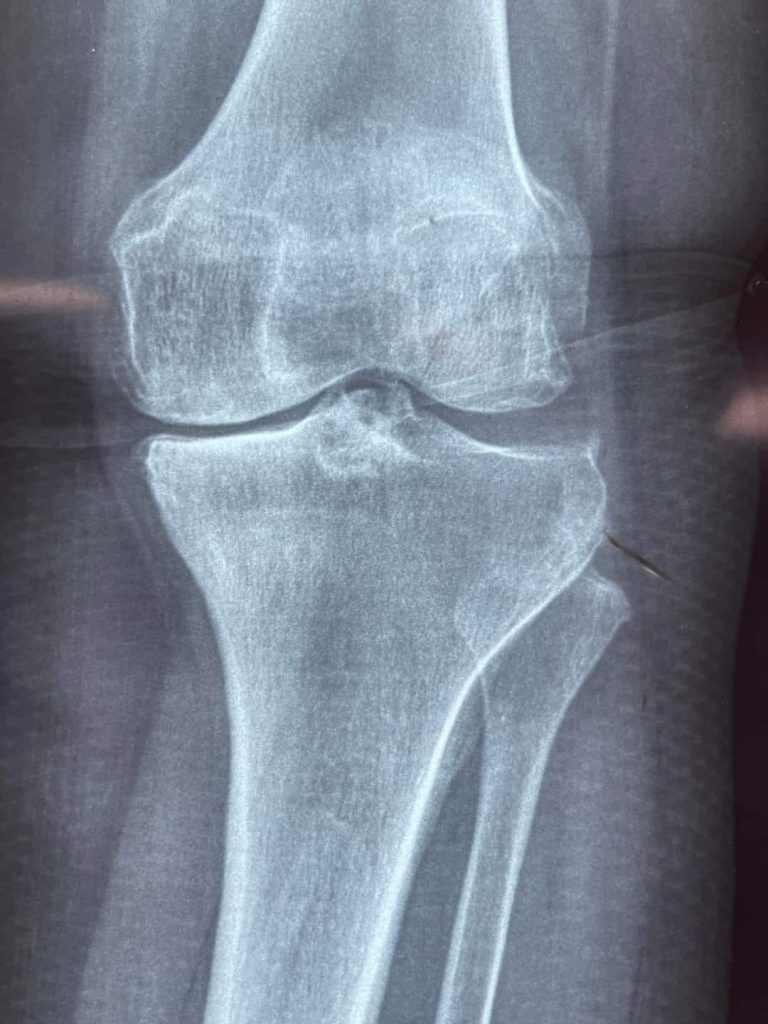

Dio inicio la jornada gratuita de cirugías de rodilla, que beneficia a 40 personas y que se realizarán en dos hospitales ubicados en Tepic: el Hospital de la Mujer, donde se atenderá a 20 mujeres, y en la UNEME, donde se llevarán a cabo las otras 20 cirugías.